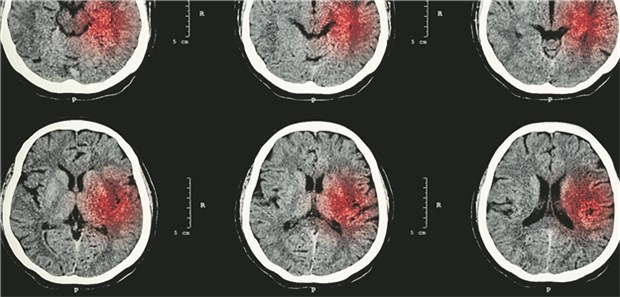

Intrakranielle Hämorrhagien traten in der Studie unter VKA früher auf als unter NOAK.

Studie

Vermehrt Hirnblutungen auch bei therapeutischen INR-Werten